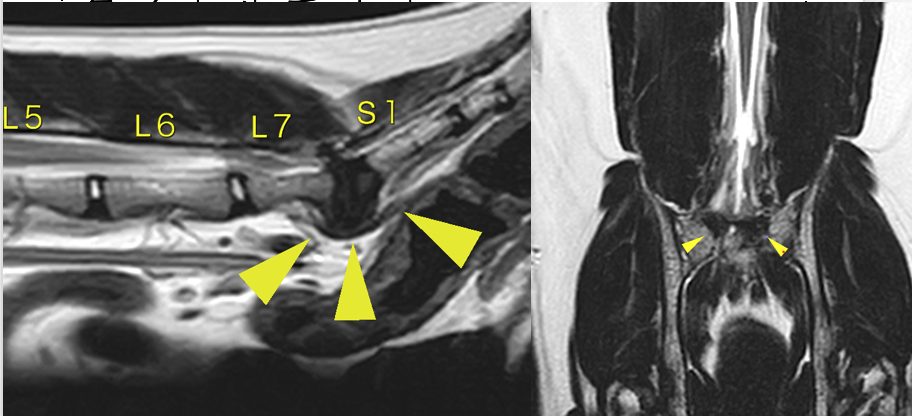

L7-S1の間に圧迫が見られます。

矢頭部が圧迫物質です(黄色靭帯の肥厚がメイン)。